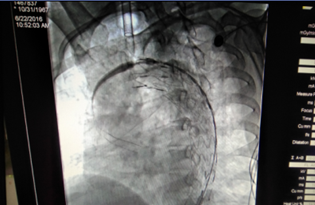

術(shù)前CT檢查(顯示為主動脈夾層)